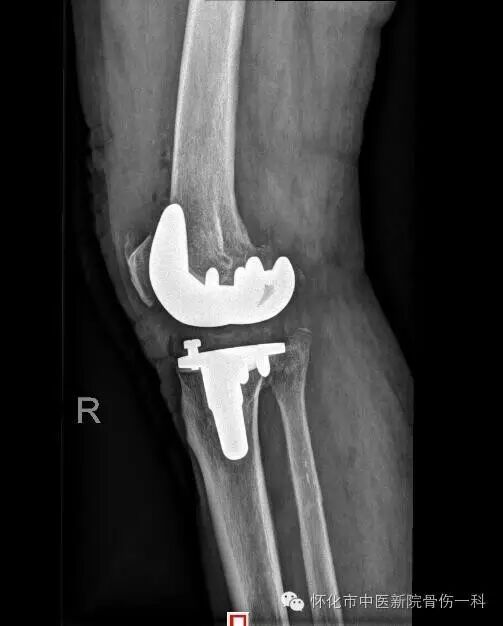

术后:

术后恢复情况:

术后第1天患者即可下地站立行走,考虑伤口情况,未让其过多运动。

术后14天伤口已愈合,拆线略有肿胀,关节活动度在0°-130°之间。下肢无浮肿,肌力达5级。